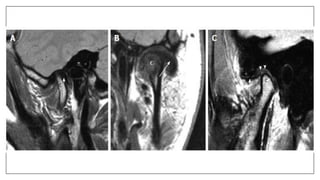

Stuck disk Phenomenon inTMJ

• A stuck disc refers to aTMJ disc which does not translate anteriorly out of

the mandibular fossa onto the articular eminence, but rather remains (thus

"stuck") in the fossa. It is a form ofTMJ dysfunction and is typically

associated with restricted range of motion.

• Its due to fibrous adhesions

Campos PS, Macedo Sobrinho JB, Crusoé-Rebello IM, Pena N, Dantas JA, Mariz AC, et al.Temporomandibular joint disk

adhesion without mouth-opening limitation. J Oral Maxillofac Surg. 2008;66(3):551-4. doi:10.1016/j.joms.2006.11.006